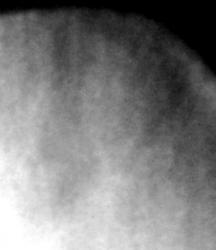

Иллюстрации 3 и 4. Определяется выраженная перестройка структуры костной ткани в области акромиального отростка, с выраженной неровностью нижнего контура и его склерозированием. В области верхне-медиальных отделов головки плечевой кости субхондрально определяется участок склероза неправильной формы в виде «языков». В верхнем наружном квадранте головки плечевой кости определяются причудливой формы участки остеопороза, местами определяются мелкие, округлой формы очаги остеопороза. Имеет место некоторая нечеткость контура в области большого бугорка.

Иллюстрации 5 и 7. Участки плечевой кости (с увеличением) – участки остеопороза без пояска остеосклероза.